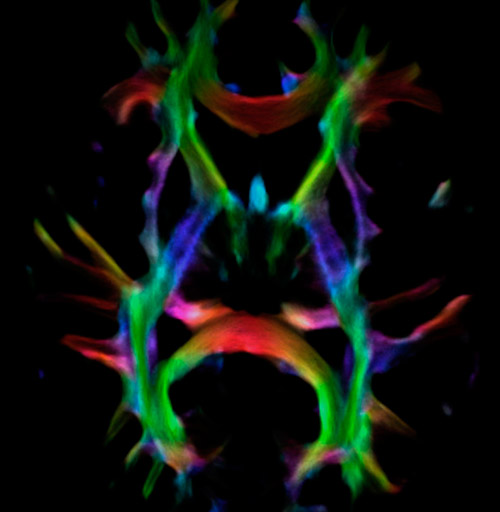

Fiber tractography of the corticospinal tract with seed region of the posterior limb of the internal capsule. Different processing based on the same data.

All images were created from the same acquisition in a child using Ingenia 3.0T CX and 32-channel dS Head coil. Diffusion data was acquired at b-values 0, 500, 1000, 2000, 3000. The use of high b-values (3000 s/mm2) effectively suppresses extra-axonal water signal and provides high angular resolution.

Data processing was performed using open source software. Fiber tracking was performed using the MRtrix package (J-D Tournier, Brain Research Institute, Melbourne, Australia, https://github.com/MRtrix3/mrtrix3), Tournier et al. 2012. DEC TDI based on F Calamante et al 2010.